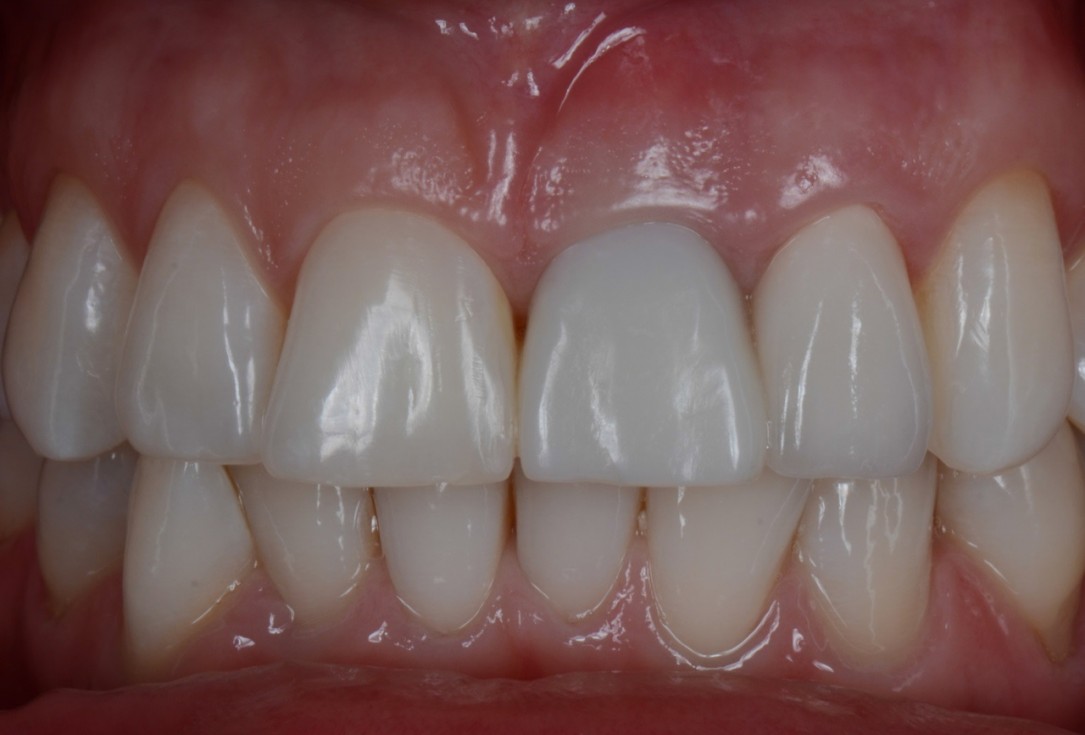

01/16 - Situation before extraction with single tooth crowns on 21 and 22